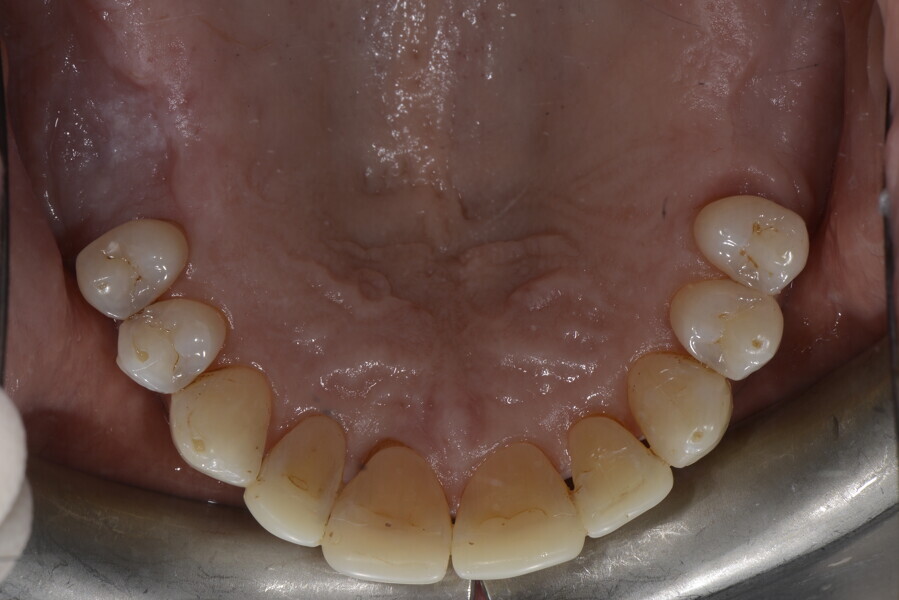

The 58-year-old patient wished to improve his oral aesthetics and function, complaining of mobility of the posterior teeth and wear of the anterior teeth. After data collection, a very complex situation was identified (Figs. 11–13):

1. severe periodontitis with poor prognosis of some teeth;

2. anterior crossbite;

3. severe wear mainly of the anterior teeth and compensatory eruption;38

4. atypical swallowing and lower posture of the tongue at rest;

5. masticatory dysfunction during the mastication test; and

6. no significant signs of temporomandibular disorder.

After the first phase of aligner treatment, we had achieved better inter-arch coherence, better maxillary arch expansion, and some space for improving the anterior tooth proportions restoratively (Fig. 19). We then temporarily restored the anterior teeth directly with composite, closing the spaces, improving the tooth proportions and further increasing the maxillary arch expansion (Fig. 20). We used restorative arch expansion to reduce the orthodontic destabilisation of the teeth to achieve the correct inter-arch coherence and retain the teeth in the cortical bone.38 A refinement aligner phase was undertaken to improve the final alignment of the gingival zenith and to improve the inter-arch coherence (Fig. 21). The periods of the first orthodontic phase and of the refinement were used to augment the mandibular and maxillary bone and to place the implants (Fig. 22). At the end of the orthodontic treatment, the case was finalised with ceramic veneers in the anterior area and temporary restorations on the implants in the posterior area (Figs. 23–26).